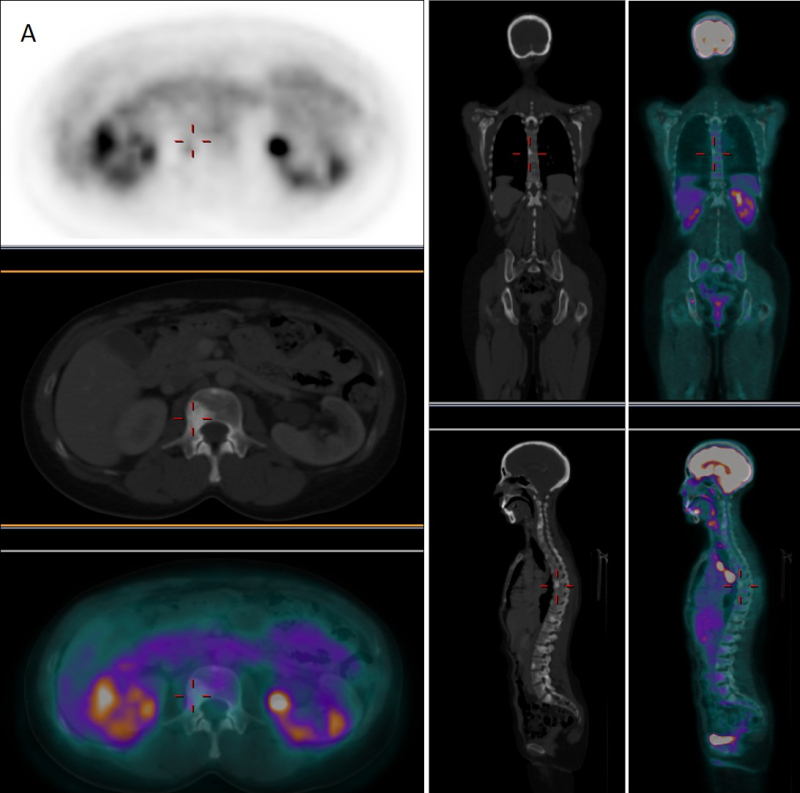

En febrero de 2019, ante la aparición de discreto dolor en cadera derecha y leve aumento del marcador tumoral CA-15-3 (35 U/mL) sospechosos de recaída, se realizó nueva GO que mostró persistencia de lesiones intensamente blásticas a predomino en columna vertebral, sin cambios respecto al estudio realizado 6 años antes (fig. 1-C). Se decidió realizar tomografia por emisión de positrones/TC con fluor-18-desoxi-D-glucosa (18F-FDG-PET/TC) para la caracterización de las lesiones invariables o detectar nuevas localizaciones sugerentes de recidiva. El estudio PET/TC (fig. 2B) demostró la presencia de una nueva lesión ósea intensamente hipermetabólica (SUVmax = 5,35) en región acetabular derecha, sin traducción aparente en la imagen radiológica, muy sugerente de recaída tumoral que justificaba la clínica y la reciente alteración analítica, mientras que el resto de las lesiones basalmente esclerosas e intensamente positivas en la GO resultaban completamente negativas desde el punto de vista metabólico (fig. 2A).

La GO se debe emplear solamente ante la sospecha de progresión, para lo cual se deben documentar al menos dos nuevas lesiones después del período "llamarada" (primeras 12 semanas) con un lapso de al menos 6 semanas(4) y no para valoración rutinaria de respuesta al tratamiento, por el riesgo de interpretación equivocada. Por otro lado, la 18F-FDG-PET/TC mide directamente la actividad metabólica de las células tumorales a través de la captación de glucosa permitiendo caracterizar los hallazgos inespecíficos de la GO, especialmente aquellas lesiones basalmente esclerosas que permanecen positivas en pacientes respondedores.

En el caso que presentamos, la GO permitió detectar correctamente diseminación ósea en el momento del diagnóstico, pero tras un adecuado manejo terapéutico, las lesiones esclerosas en TC continuaron exhibiendo durante años intensa actividad osteogénica, difícilmente interpretable en un contexto de remisión clínica y analítica. Sin embargo, ante una sospecha real de recaída tumoral, el estudio gammagráfico no demostró aparición de nuevas lesiones ni modificación de las previamente existentes. Por su parte, la PET permitió descartar viabilidad tumoral en las lesiones sospechosas en las técnicas de imagen convencional, permitiendo la detección de recaída ósea a través de una nueva lesión hipermetabólica que explicaba la aparición de signos analíticos y clínicos de recidiva.

De la misma manera, en otros estudios la 18F-FDG-PET/TC ha demostrado mayor precisión en la monitorización de respuesta al tratamiento en enfermedad ósea metastásica, presentando una adecuada concordancia entre imágenes y síntomas en los pacientes con enfermedad controlada(5,6,8). La actividad metabólica focal traduce enfermedad no controlada, mientras que la resolución de dicha actividad indica respuesta al tratamiento, independientemente de la apariencia en la GO o TC. Sin embargo, la reacción en “llamarada" en la médula ósea también se ha descrito con PET/TC tras el empleo de factor estimulante de colonias de granulocitos para prevenir o tratar la neutropenia asociada a la terapia. Igualmente, este fenómeno se ha observado 7 a 10 días después del inicio de la terapia con tamoxifeno o fulvestrant en el cáncer de mama RH positivo, lo cual puede indicar el éxito final de la terapia. En cualquier caso, un aumento de la esclerosis en las lesiones a lo largo del tiempo sin aumento del SUV generalmente se asocia a una respuesta favorable verdadera.